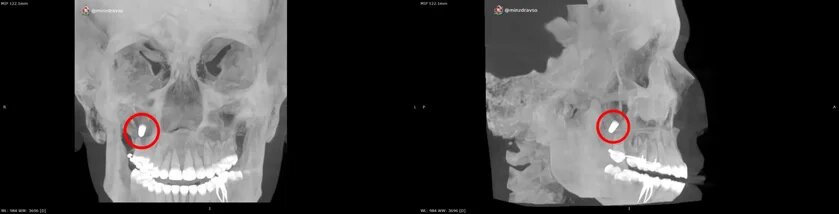

Специалисты медицинского центра «Бонум» извлекли из верхних отделов гайморовых пазух пациентки металлический имплант, который ей пытались установить несколько месяцев назад, но в итоге просто протолкнули к носу. Об этом сообщила пресс-служба Минздрава Свердловской области.

Этот случай стал продолжением пятилетней истории хождения по стоматологическим мукам 37-летней жительницы Свердловской области. Всё началось с удаления зуба из-за осложнённого кариеса. Не обошлось без проблем, которые в итоге привели к операции по наращиванию кости верхней челюсти. Спустя месяцы, при попытке установки дентального имплантата произошёл инцидент с его проталкиванием в правую верхнечелюстную пазуху.

«Имплант должен быть вкручен в кость. При детальном осмотре выяснилось, что у пациентки, говоря простым языком, практически некуда было вкручивать металлоконструкцию, потому что синус-лифтинг не принёс желаемого эффекта, наращенной костной ткани оказалось недостаточно», — прокомментировал зав. отделением реконструктивной и пластической хирургии центра «Бонум» Вадим Бродовский.

На фоне патологии у женщины появились периодические боли и дискомфорт. Присутствие инородного тела могло привести к серьёзному воспалительному процессу, усилению болевого синдрома и кровоточивости.

Операционная бригада во главе с Вадимом Бродовским успешно выполнила эндоскопическое удаление импланта из правого верхнечелюстного синуса. Удаление прошло не по «классической» гайморотомии за губой, как обычно, а через полость носа, без разрезов за губой и дефектов передней стенки пазухи.